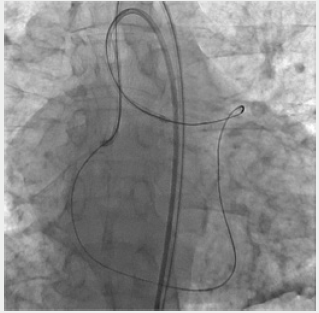

Figure 6: Retrograde recanalization of service stations. The procedure of externalization. Occlusion of PKA. Through the septal collaterals, a conductor and a microcatheter were conducted to the distal part of the PCA, then through the occluded segment to the antegrade operating catheter.